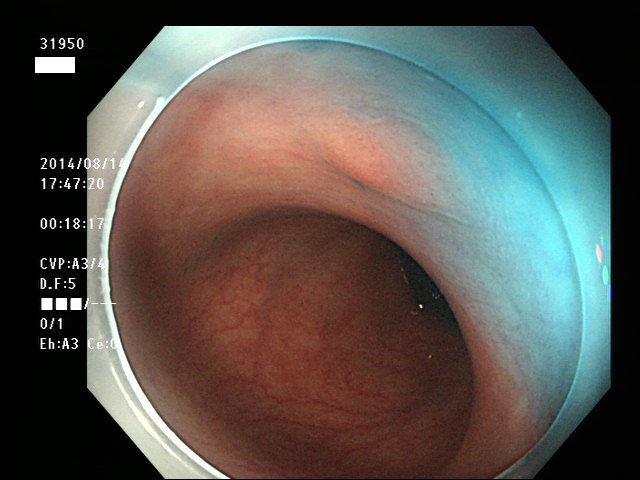

上記100名より抽出した平坦・陥凹型腺腫(=癌化の危険が高いが見落としやすい病変)の内視鏡写真